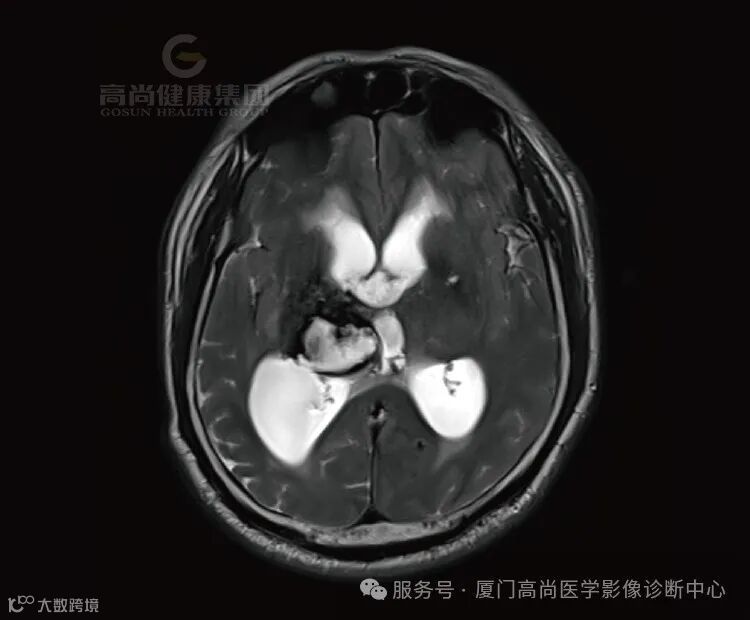

1.右侧丘脑、基底节、放射冠区病灶,考虑脑出血(亚急性期)并破入右侧脑室,中线结构局部左偏,请结合临床。

(2)亚急性晚期(1-4周):T1和T2上均呈高信号,灶周水肿,占位效应逐渐减轻。

在MRI 上血肿周围脑水肿呈 TIWI 低信号、T2WI高信号,血肿周围脑水肿一般在发病后3~4d至第1周末最显著,以后逐渐减轻。约1个月后血肿开始消退。一般在2个月左右进入囊变期,此时血肿完全吸收,周围水肿完全消失,原血肿变为脑脊液的囊腔,即软化灶(T1WI呈低信号,T2WI呈高信号),与此同时出现邻近脑室、脑沟增宽等萎缩性改变。数月或更长一段时间后,可仅残存窄带状或局灶性小囊腔,小血肿甚至可完全被胶质瘢痕代替而消失。